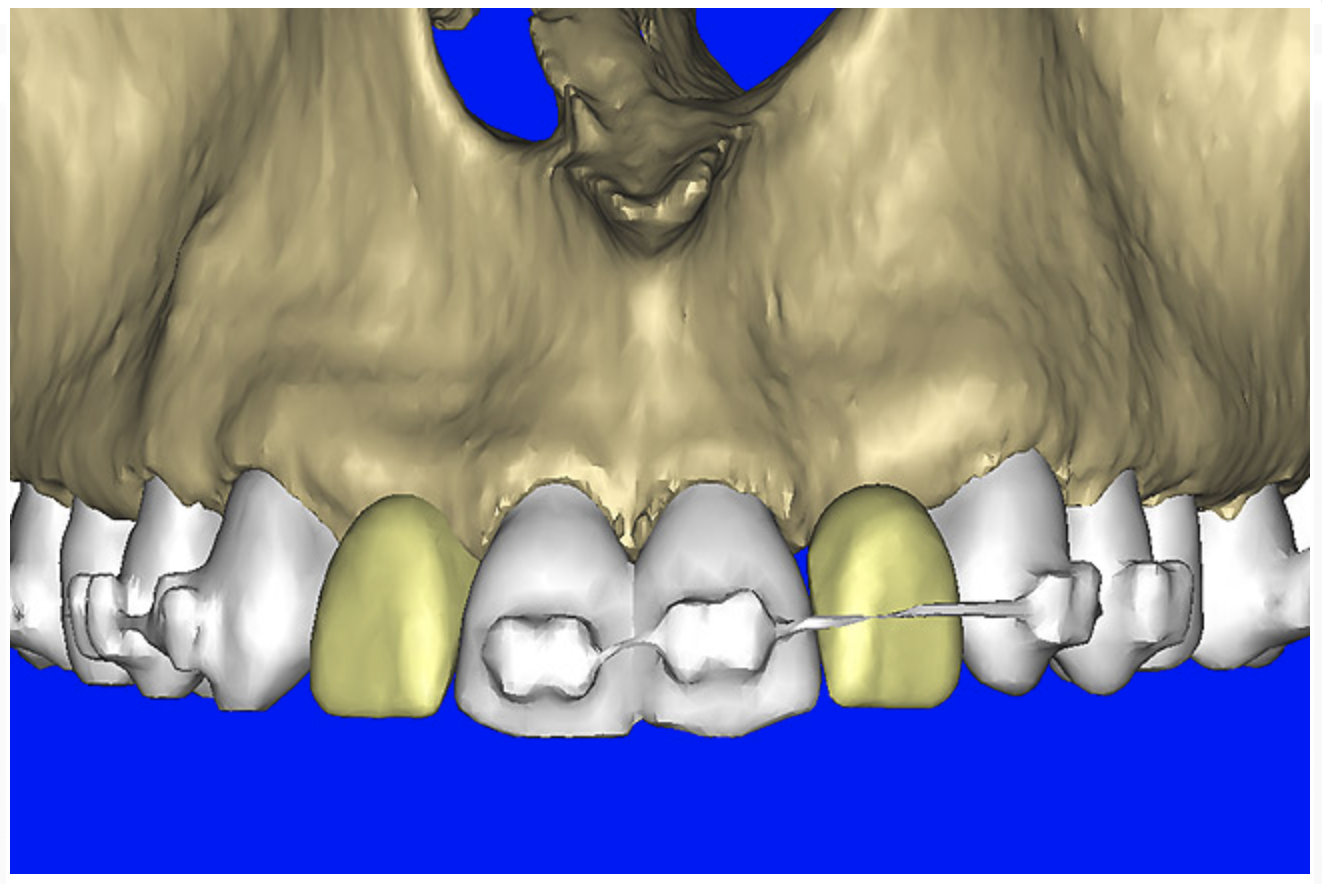

However with all of this preliminary planning, the most important aspect was yet to be addressed—the relationship of the bone, implant, and abutment to the final restoration, the implant crown. Before the advent of interactive treatment-planning software applications, the only reliable method to incorporate tooth information was through a scannographic radiopaque template worn by the patient during the scanning process. This highly desirable planning aid required prior laboratory preparation. While still in its early phase of implementation, the use of a virtual tooth tool provided an additional innovative 3D planning aid, which was used for this case. Virtual teeth allowed for a final inspection of implant and abutment positioning, without a scanning appliance (Figure 10A). The abutment projection was evaluated for a cementable prosthesis (Figure 10B) and, if it had been required, the abutment easily could have been changed to an angulated version. (The software provides the ability to customize the degree of inclination.) The final shape of the virtual teeth can be seen in Figure 10C. The combination of interactive 3D models, multiple volume renderings, realistic implants, realistic abutments, and virtual teeth created a powerful set of tools in the author’s quest to achieve true restorative-driven implant dentistry defining new paradigms for assessing patient anatomy for implant planning.

Figure 10a  By using the virtual teeth feature, (A) final implant and abutment positioning was checked, (B) the abutment projection evaluated for a cementable prosthesis, and (C) the appearance of the desired virtual restorations evaluated for emergence and esthetics.

Figure 10a

Figure 10b  By using the virtual teeth feature, (A) final implant and abutment positioning was checked, (B) the abutment projection evaluated for a cementable prosthesis, and (C) the appearance of the desired virtual restorations evaluated for emergence and esthetics.

Figure 10b

Figure 10c  By using the virtual teeth feature, (A) final implant and abutment positioning was checked, (B) the abutment projection evaluated for a cementable prosthesis, and (C) the appearance of the desired virtual restorations evaluated for emergence and esthetics.

Figure 10c